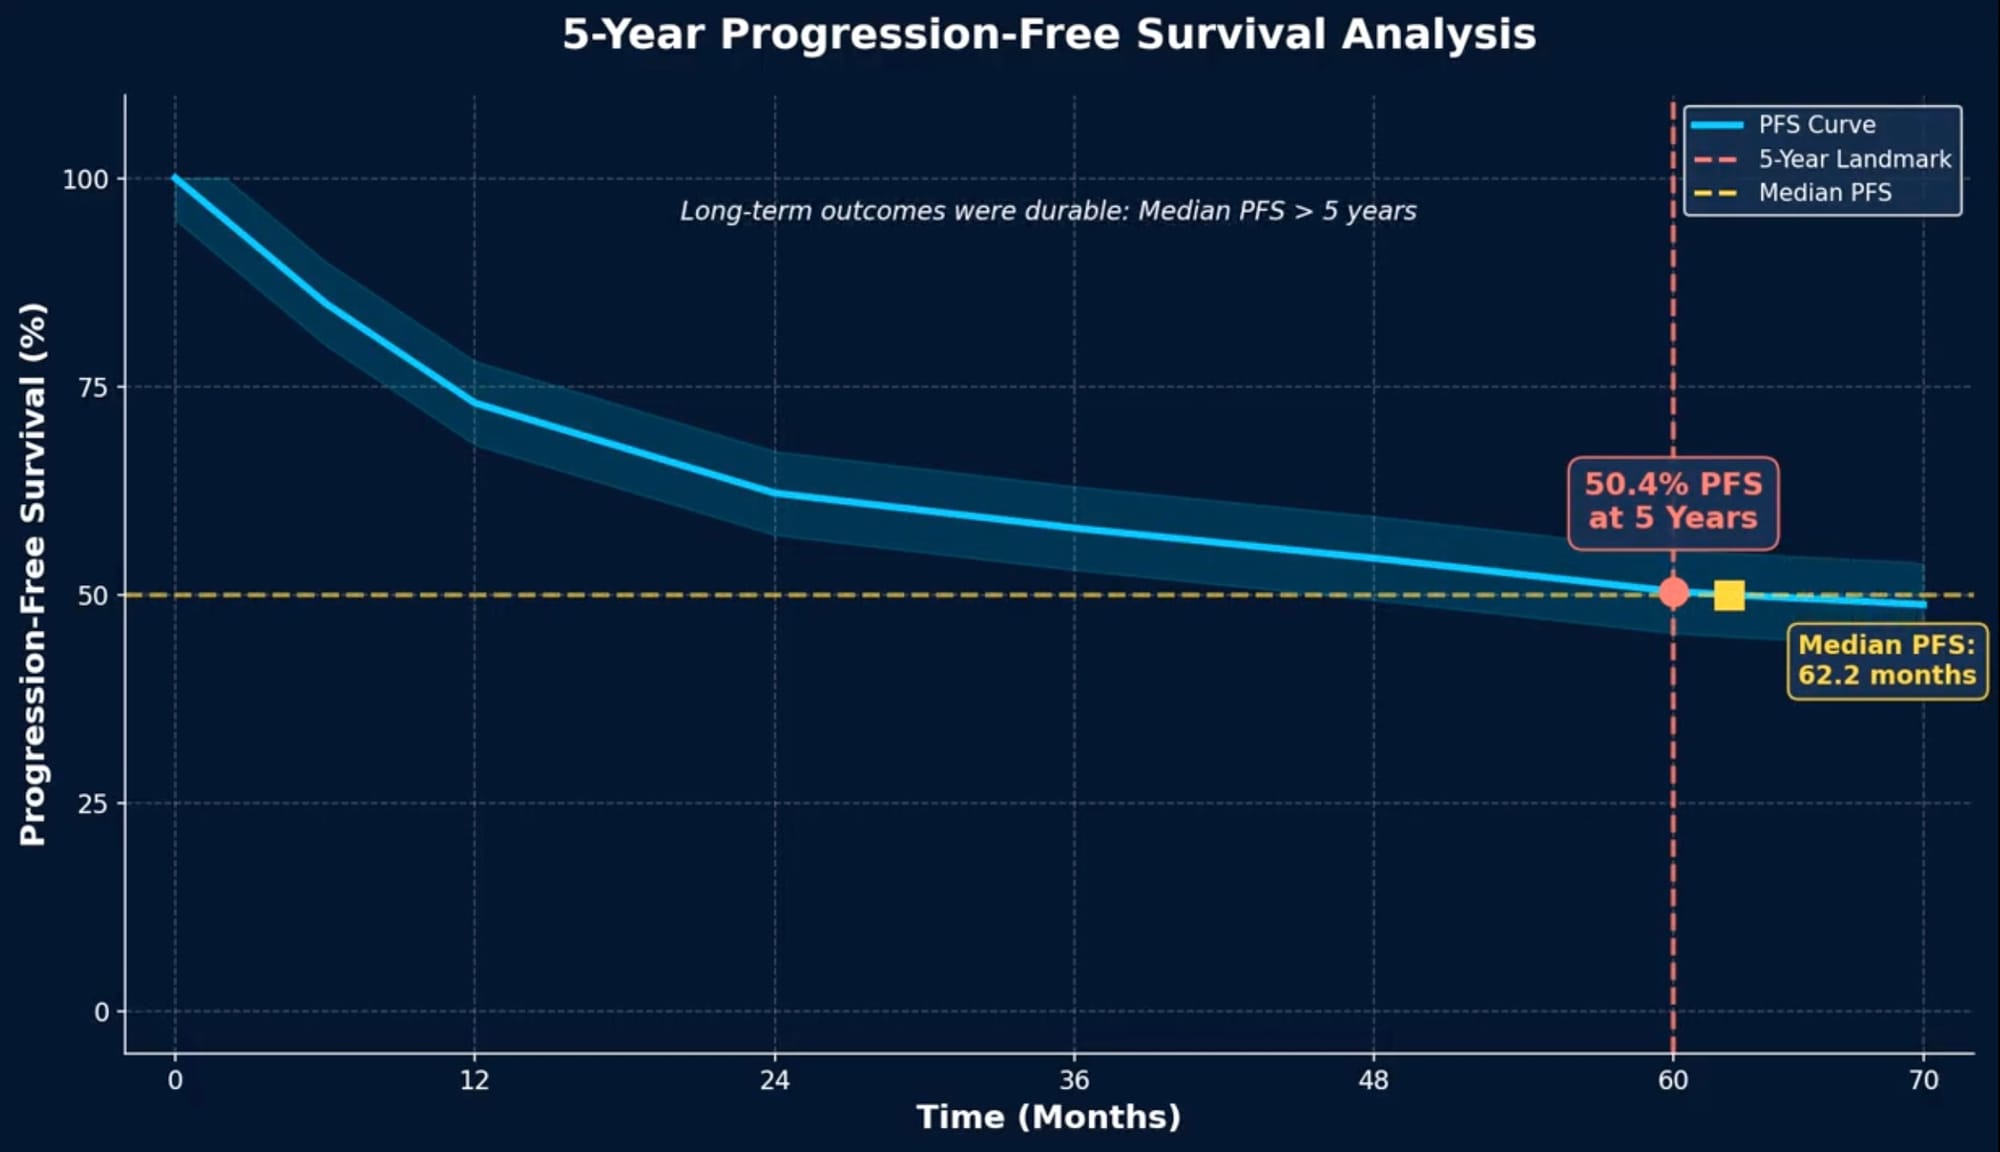

Durability proved to be the defining feature of these results:

- Median duration of response: 60.4 months

- Median progression-free survival: 62.2 months

- 50.4% of patients reached the 60-month progression-free survival landmark

A plateau in lymphoma-specific outcomes: The investigators observed that after 30 months post-infusion, progression or lymphoma-related deaths became rare—only two such events occurred beyond this timepoint. This plateau suggests that patients who remain in remission at 2.5 years have a high likelihood of sustained disease control, a pattern consistent with potential curative benefit for a subset of patients.

Comparison to historical benchmarks: While cross-trial comparisons require caution, the median progression-free survival of 62.2 months in ZUMA-5 compares favorably to outcomes typically seen with salvage chemoimmunotherapy in relapsed follicular lymphoma, where median PFS generally ranges from 12 to 24 months depending on the regimen and patient selection.

The plateau phenomenon: Unlike in diffuse large B-cell lymphoma where a clear survival plateau emerges around two years post-CAR T, the pattern in follicular lymphoma is more gradual—partly because of the longer latency before progression events manifest clinically and competing risks of death from other causes. Lymphoma-specific progression-free survival may more accurately capture the curative potential in this disease.